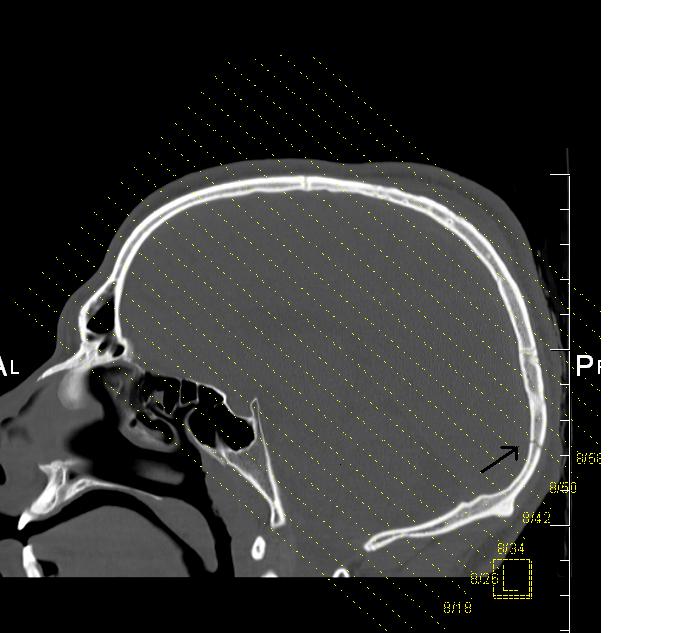

The 22-year-old man was taken to Liverpool Hospital in a critical condition, suffering a fractured skull and bleeding to the brain.

In addition to a fractured and lacerated skull, Mr Rajasuriar sustained abdominal injuries and fractured ribs.

Mr Rajasuriar was taken to Liverpool Hospital, where he remains seriously ill; he underwent surgery for bleeding to the brain, and is currently reported to be in an induced coma and in a critical condition.